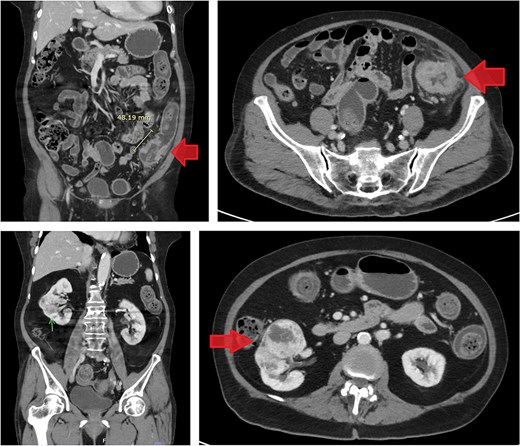

CT scan of the abdomen revealed a short segment of irregular, circumferential wall thickening at the distal descending colon, measuring 1.8 cm in thickness and extending 4.8 cm in length. Moreover, it was associated with an adjacent soft tissue lesion and perilesional fat stranding. Chest CT imaging demonstrated the absence of lymph node enlargement and pulmonary metastatic lesions. Incidentally, a 6.6 cm heterogeneous, hypervascular mass was detected in the interpolar region of the right kidney, abutting the anterior renal fascia (Fig. 3).

Contrast-enhanced CT images of case 2. Top-left: Coronal view of the sigmoid colon cancer. Top-right: Transverse view of the CRC. Bottom-left: Coronal view of the RCC. Bottom-right: Transverse view of the RCC.